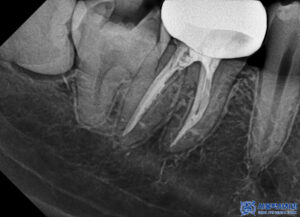

또한 치아 뿌리까지 노출된 상태였고

신경 오염이 많이 된 상태여서

자연치아를 살리기에 많은 노력이

필요한 상황이었습니다.

해당 부위는 신경치료를 진행하여

깊은 충치로 인한 치아 내부의

감염을 제거하고 치아의 기능을

회복할 수 있도록 했습니다.

본원은 MTA 신경치료를

진행하고 있습니다.

본원 신경치료의 경우,

보이지 않는 곳일지라도

좀 더 좋은 재료를 사용하여

하나를 치료해도 제대로 하고자

노력하고 있습니다.

특히 일반적으로 신경치료할 때

고무성분으로 충전하여

마무리를 하곤 하는데,

본원은 MTA라는 바이오세라믹 성분을 사용하여

신경치료를 하고 있습니다.

MTA 신경치료의 경우

재료비 훨씬 비싸지만,

장점이 훨씬 많고 좋은 예후를

기대할 수 있어서

서울박사치과에서 고집하는 재료입니다.